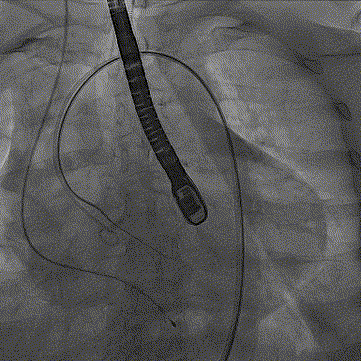

手术影像:

导丝顺利跨瓣

严重横位心,输送器无需

snare顺利跨瓣释放